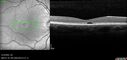

Pseudophakic cystoid macular edema (CME)158 views66 year old female 4 months following cataract surgery. Never had very good vision after surgery. On PF QID for one month. VA 20/50 in both eyes.